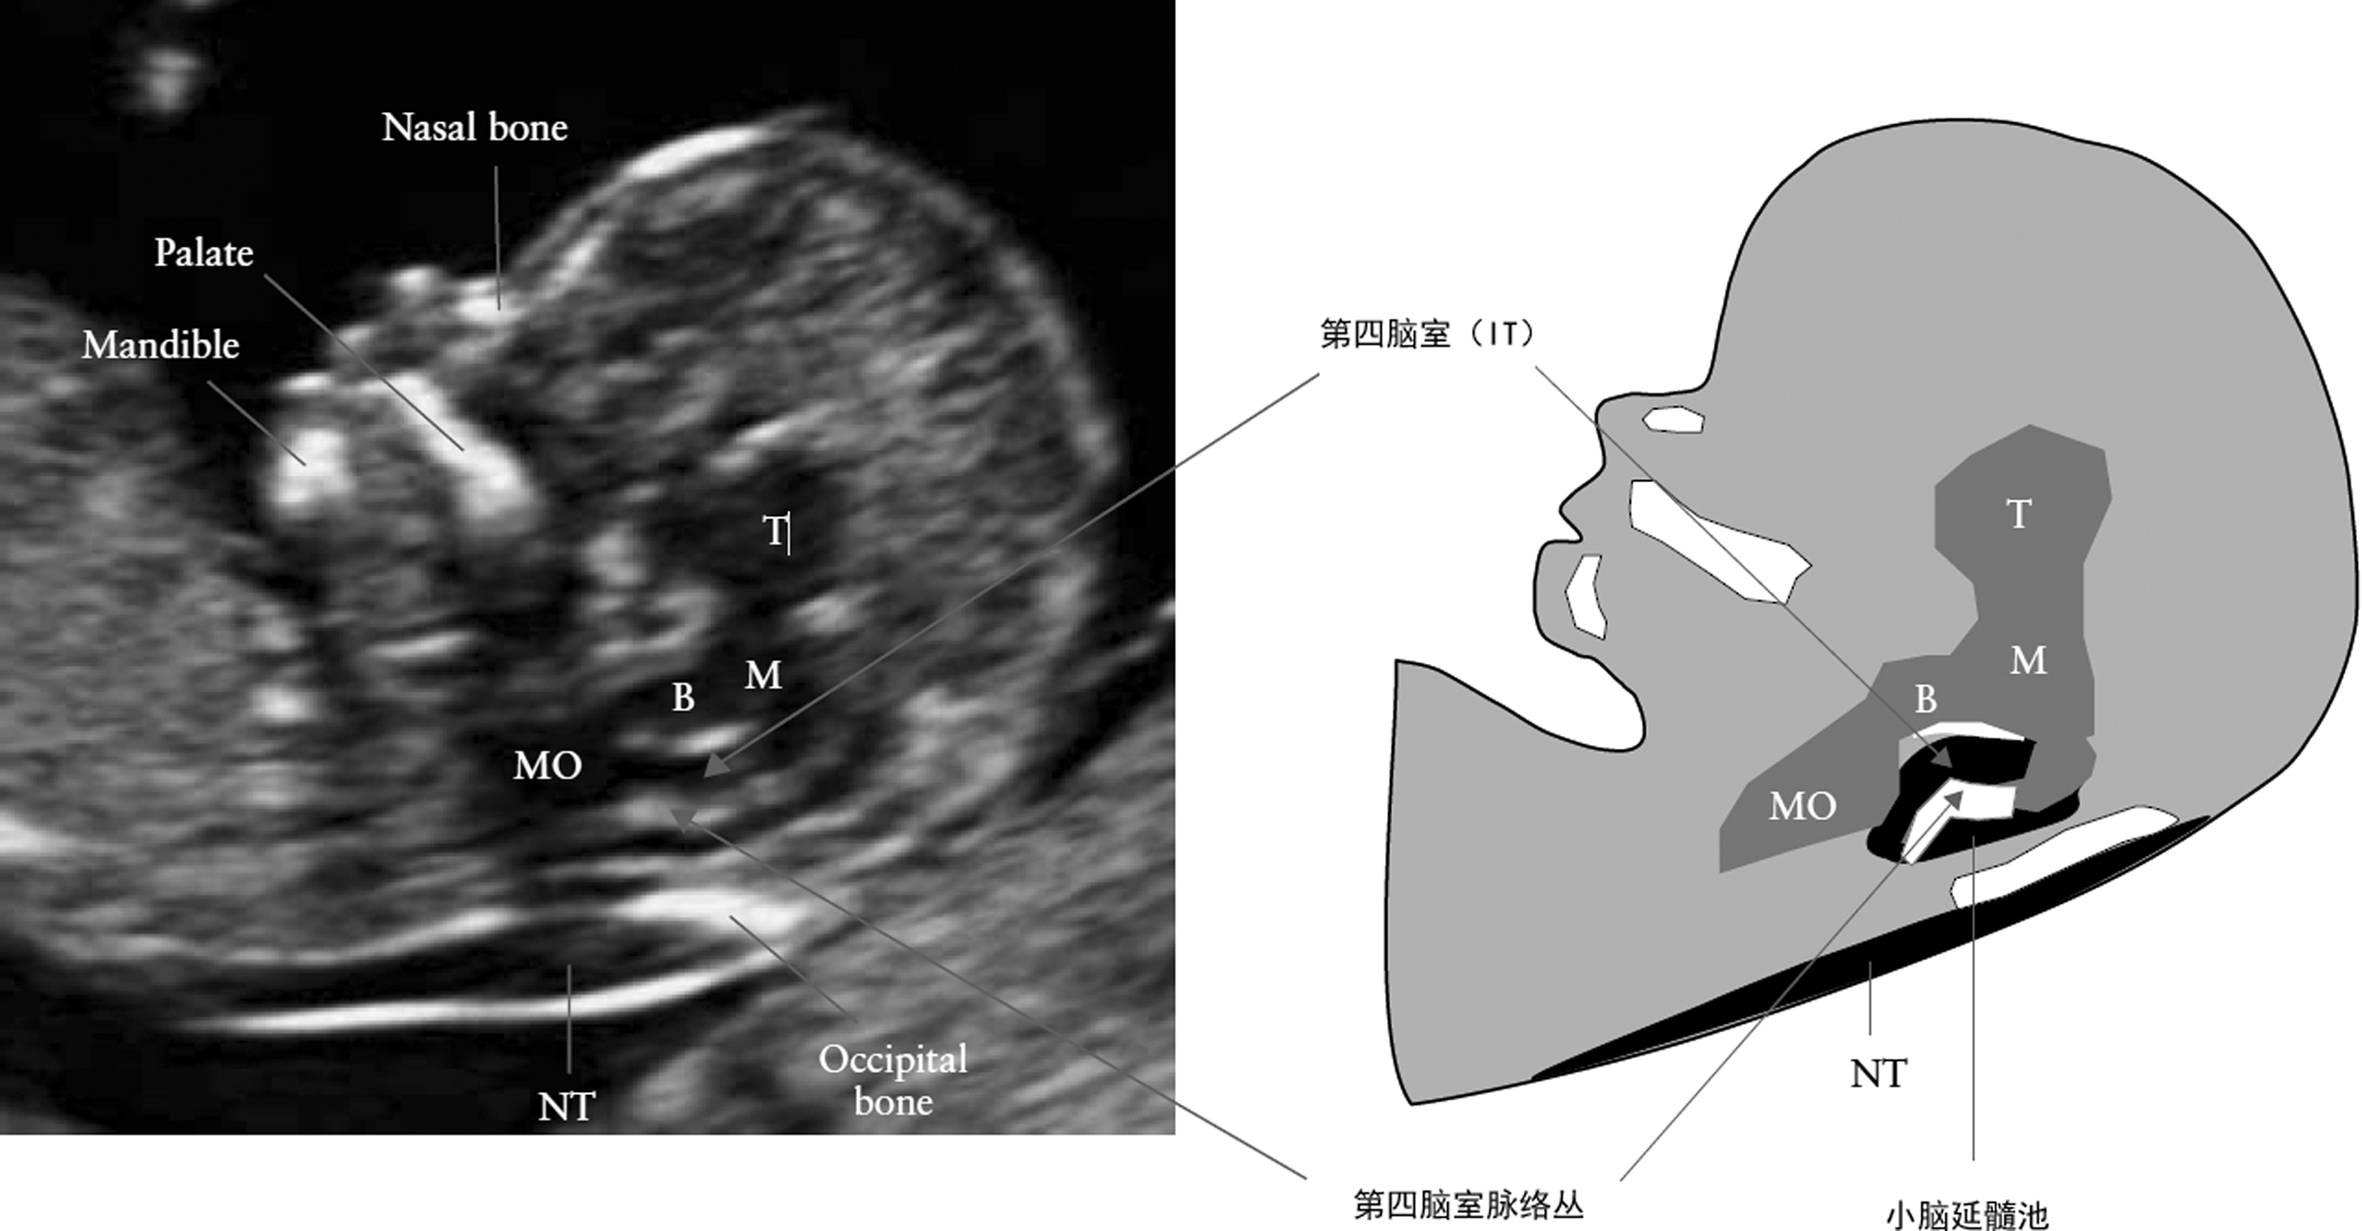

早期妊娠期胎儿头部即显示典型的头部颅骨环回声(图1A)。第11孕周时颅骨出现骨化,颅骨环呈断续的强回声,骨的边缘连接处未骨化区域显示为低回声。颅骨环内长轴上可见断续的中线强回声,垂直于中线的颅骨环强回声外缘之间的距离为双顶径(BPD),垂直于双顶径的颅骨环强回声外缘之间的距离为枕额径(OFD)。在此断面上颅内最显著的回声是侧脑室(图1B)。侧脑室后2/3由强回声的脉络丛充满,脑室与颅骨环之间的低回声主要由脑实质形成;中线两侧对称;两侧小脑半球在中线处开始联合,超声显示为两端略大,中间略窄的低回声结构;颅内其他结构胼胝体、第三脑室、中脑、脑干及小脑延髓池等可以显示,但由于没有发育完全难以进行准确的评估;有研究者提出了以正中矢状面显示第四脑室的前后径作为颅内透明层(IT)评估开放性神经管缺陷(图2),有待于积累更多的资料。

图2 胎儿颅内透明层

(图中:Nasal bone:鼻骨;Palate:上腭;Mandible:下颌骨;B:脑干;IT:颅内透明层;M:中脑;T:丘脑;MO:延髓;Occipital bone:枕骨;NT:颈部透明层)

妊娠9~10周可显示上颌骨及下颌骨,10~11周可显示眼眶回声。11周显示眼球内晶体呈极小的圆形小结构,14周显示率明显增高。在6~12周之间,颜面部矢状面变化较大,第7周前额骨明显突出,上颌骨生长明显快于下颌骨生长,因而显示上颌骨较下颌骨明显增大,到第12周下颌骨生长才赶上上颌骨,达上颌骨大小。鼻、唇、腭形成最晚,鼻、唇在11周才完全形成,腭到12周才发育完全。因此,12周后,胎儿颜面部的解剖结构基本建立,使用高分辨力超声检查可以显示(图2)。

在面部的正中矢状面可以显示典型的胎儿额部、鼻部、上颚、口唇、下颌等连续性结构,轮廓显示清晰而典型,眶腔横断面检查可以显示眼眶及晶体;在适当的断面上可以显示鼻骨、上颌骨以及口唇的完整性但难以在此期做出准确的评价。